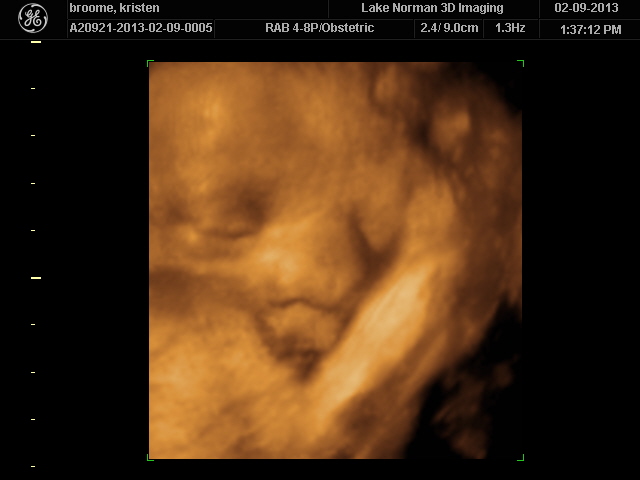

..We meet again, little boy!